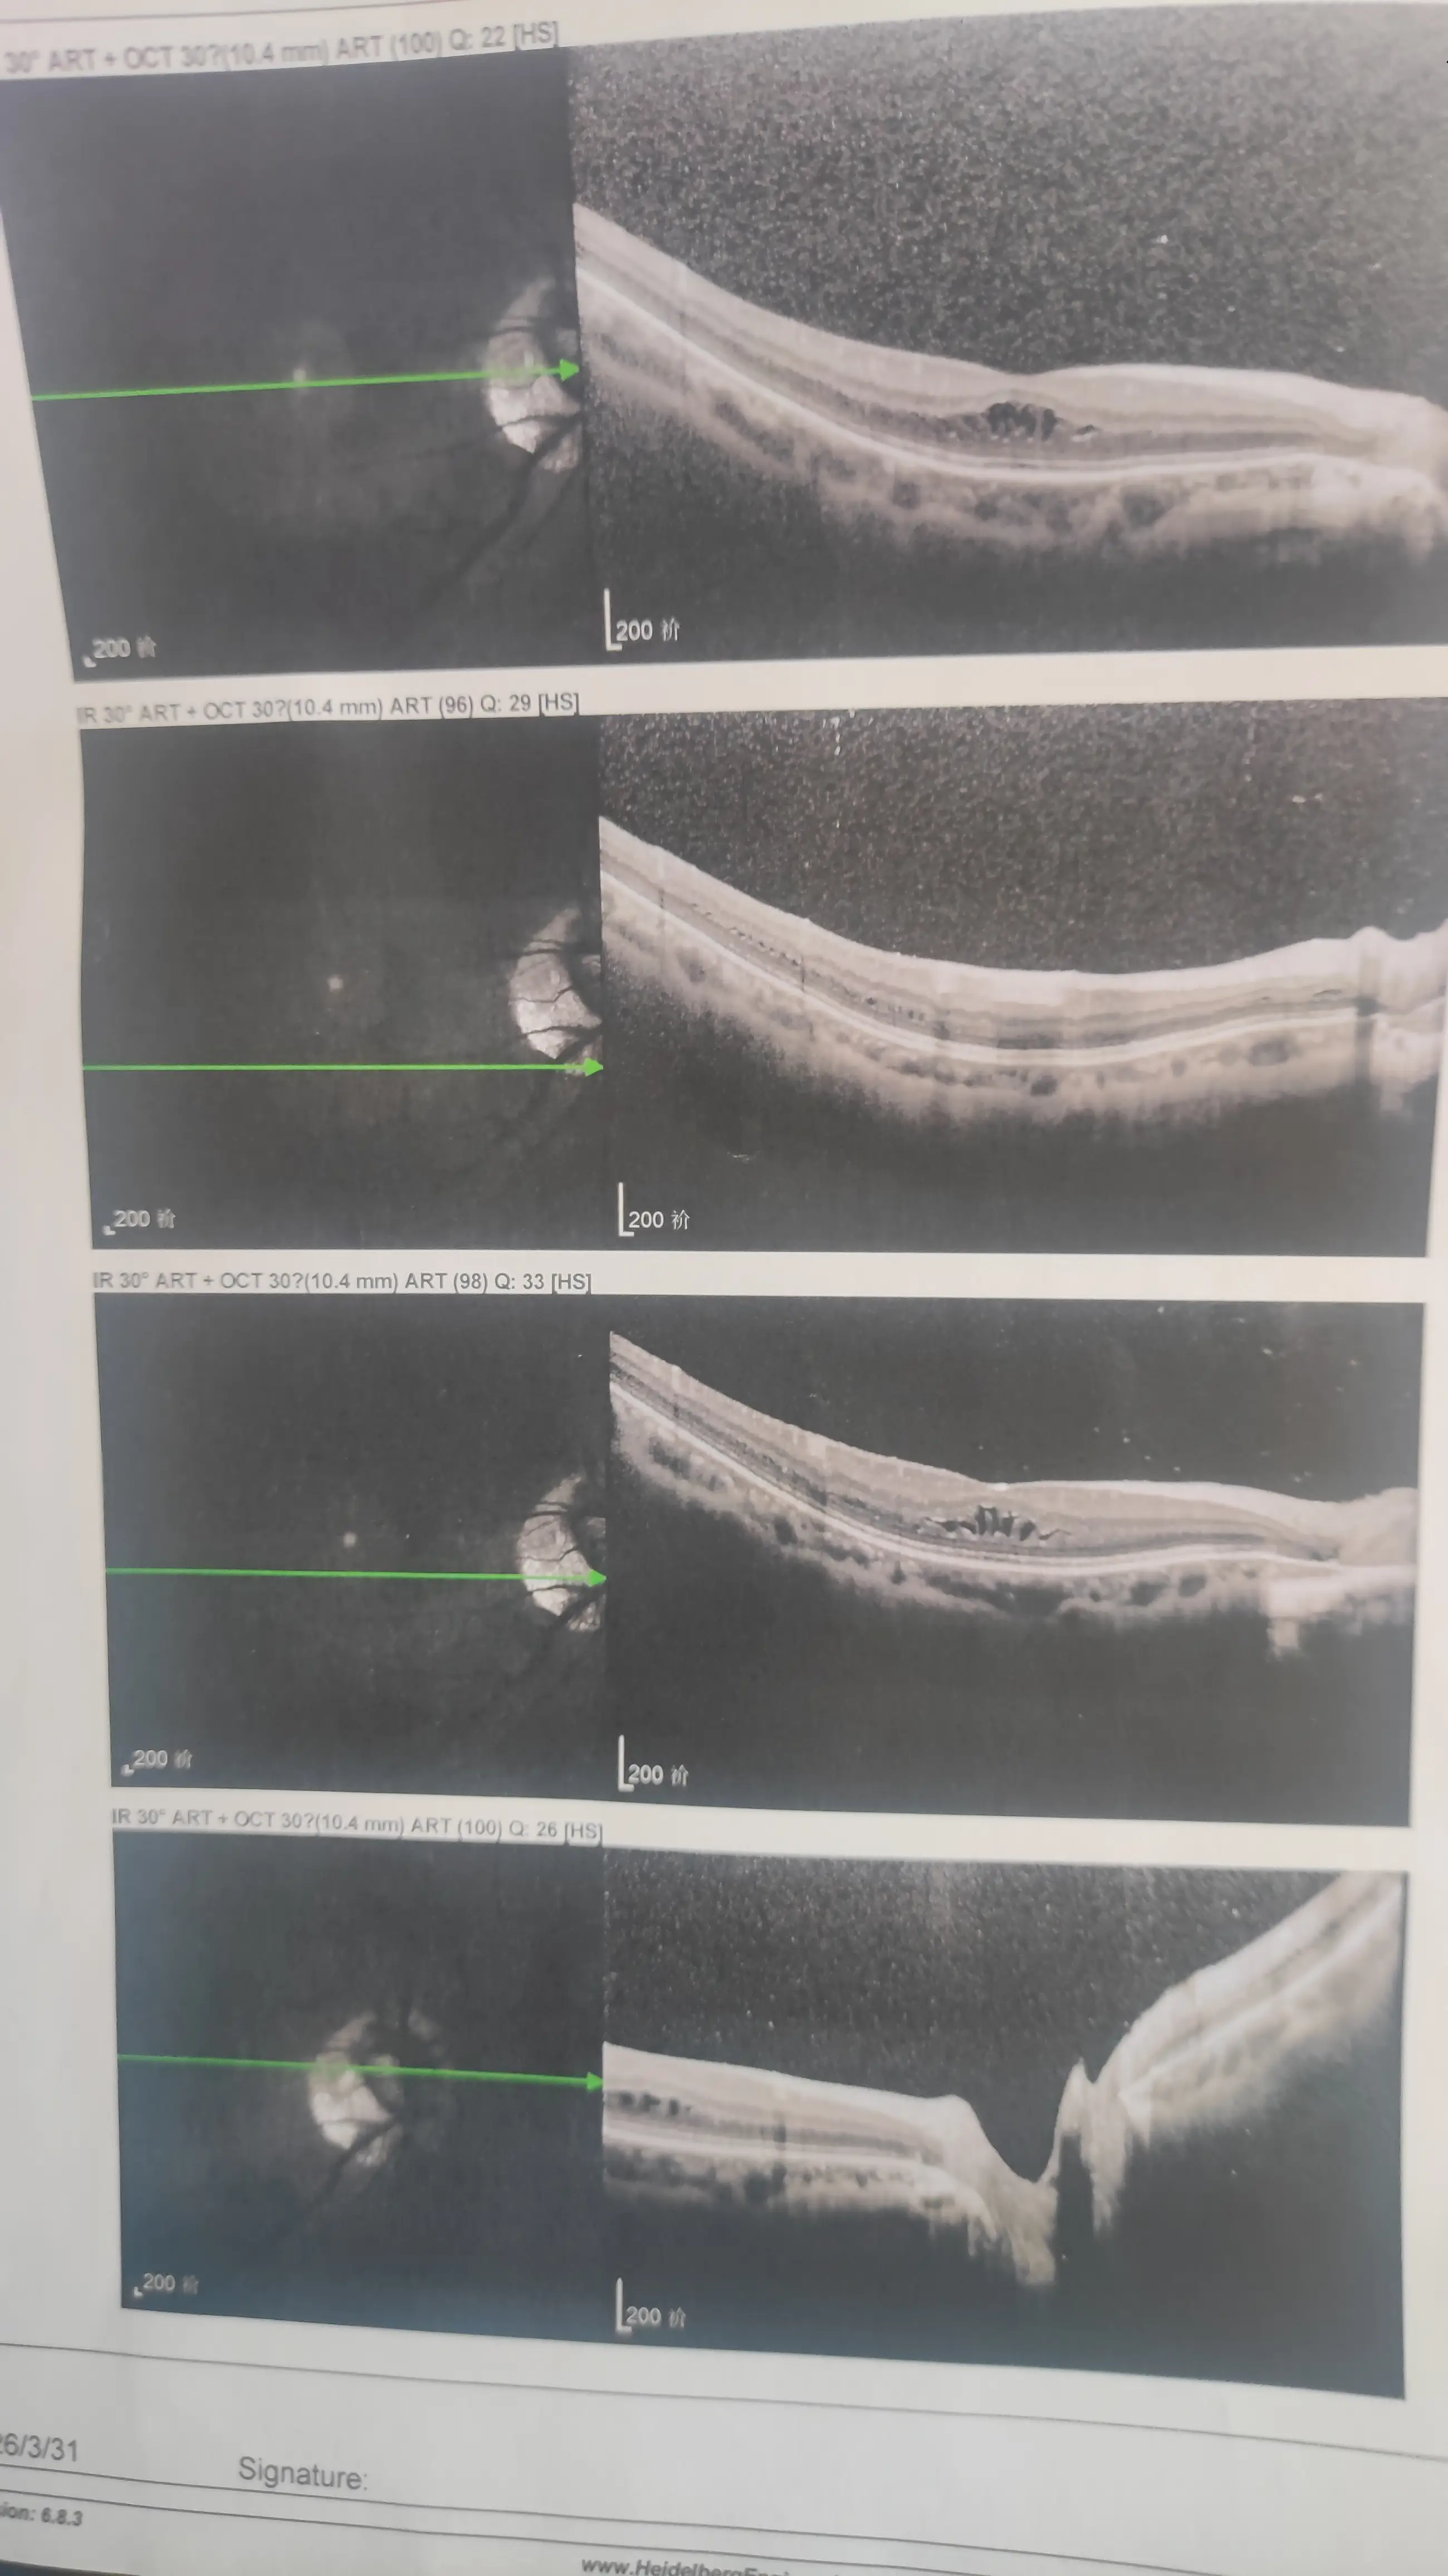

然后就喜提了一个坏消息:视网膜脱落。

希望你们都能好好的,如果有和站长一样,高度近视的,一定要定期去医院检查一下眼底。

提前发现的话,不仅治疗简单,花费也少。

最后,给大家看一下病例吧,以示警戒,希望大家关爱用眼健康!